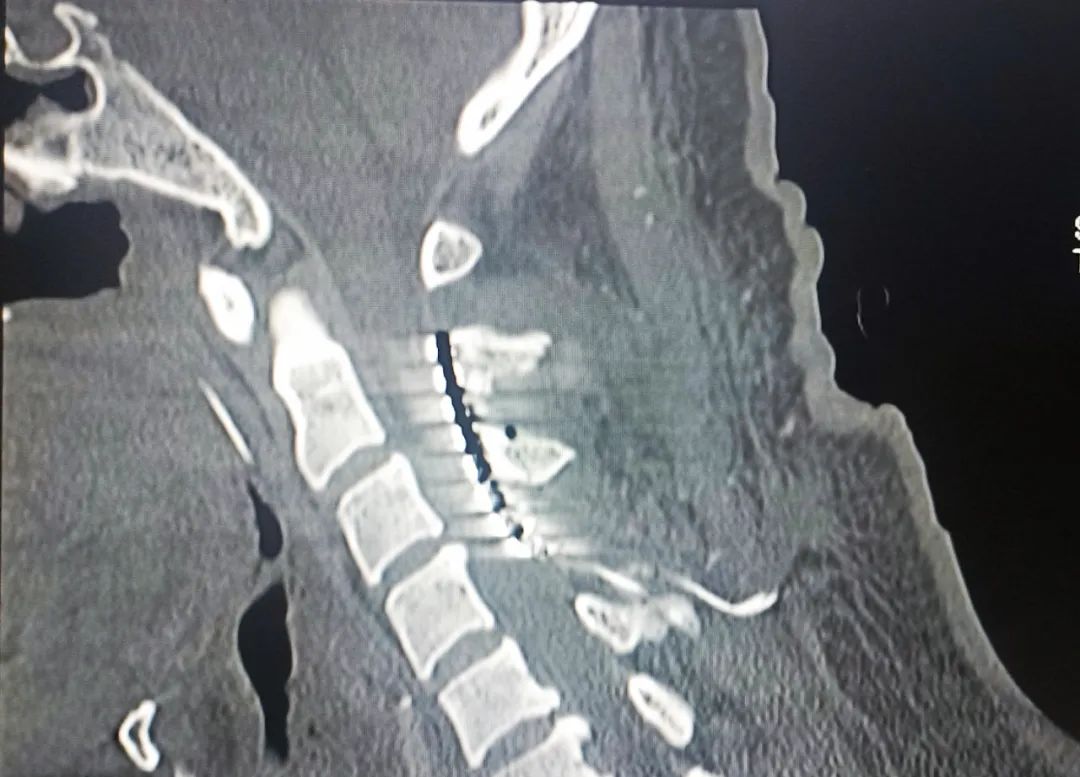

患者,男,37歲,4個(gè)月余前因“腦干出血”入住我院,經(jīng)過(guò)多次搶救治療,雖然保住了患者性命,但一直處于昏迷狀態(tài)。續(xù)繼軍主任和吳開福主治醫(yī)師,經(jīng)過(guò)全面評(píng)估及充分的溝通后,對(duì)患者實(shí)施脊髓電刺激手術(shù)促醒治療。該手術(shù)具有創(chuàng)傷相對(duì)小,安全性高,術(shù)后床旁開機(jī)程控操作簡(jiǎn)單等優(yōu)點(diǎn)?,F(xiàn)術(shù)后開機(jī)程控一個(gè)月,患者的意識(shí)障礙及肢體活動(dòng)等情況得到不同程度改善。